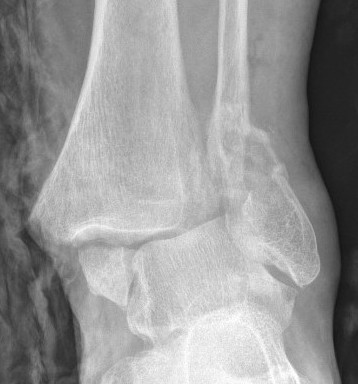

| Bimalleolar fractures | Trimalleolar fractures |

Fibular + medial malleolus Fibular + posterior malleolus |

Fibular + Medial malleolus + Posterior malleolus |

Bimalleolar fractures

Medial malleolus + Weber B lateral malleolus

Medial malleolus + Weber C lateral malleolus

Tri-Malleolar Fracture

Lateral malleolus + medial malleolus + posterior malleolus